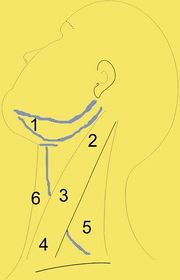

| 15:52, 22 October 2018 | Levels.jpg (file) |  |

14 KB | Drtbalu | |